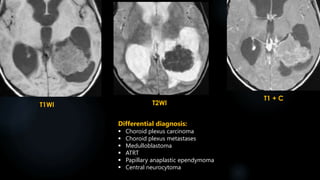

T1WI T2WI

T1 + C

Differential diagnosis:

 Choroid plexus carcinoma

 Choroid plexus metastases

 Medulloblastoma

 ATRT

 Papillary anaplastic ependymoma

 Central neurocytoma